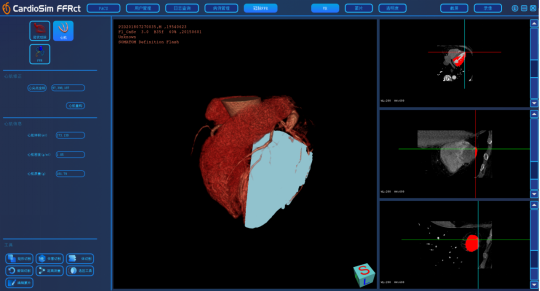

产品简介:

我司CardioSim FFR 产品,基于冠状动脉CT影像定量计算获得冠状动脉FFR,预期供培训合格的医疗技术人员用于成人患者冠状动脉病变血管的功能学评价。临床中还应结合患者的临床病史、症状、其他诊断结果和临床医生的专业判断来综合评价冠状动脉血管。软件核心包扩冠脉中心线提取,心肌重构以及FFR计算。针对造影剂不足的冠脉,如果重构出现分支断裂,可以进行修复连接。同时,包含对冠脉点云的切割等多种功能,确保在FFR计算之前,冠脉的形态学能得到的还原。